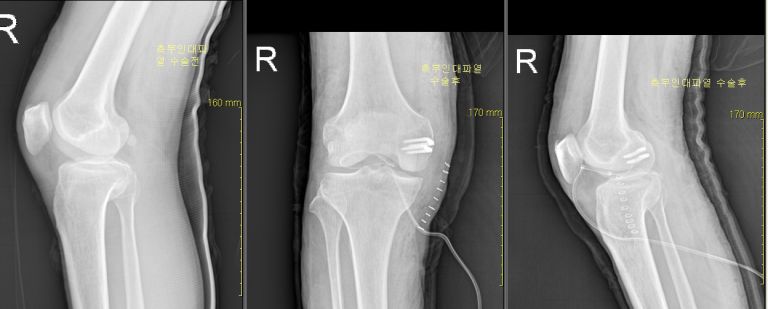

전방십자인대파열 복원술